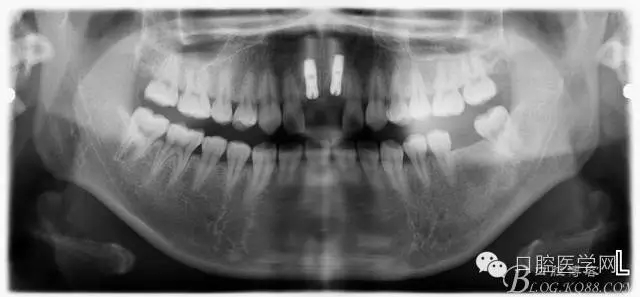

設(shè)計(jì)方案:11.21種植(選用登騰系統(tǒng),GBR植骨)12.22 RCT后樁冠修復(fù),牙齦瓷修復(fù)。

一期手術(shù)后3-6個月可做二次修復(fù),接愈合基臺,拆線后10-15天根據(jù)情況可以采模型做牙冠。